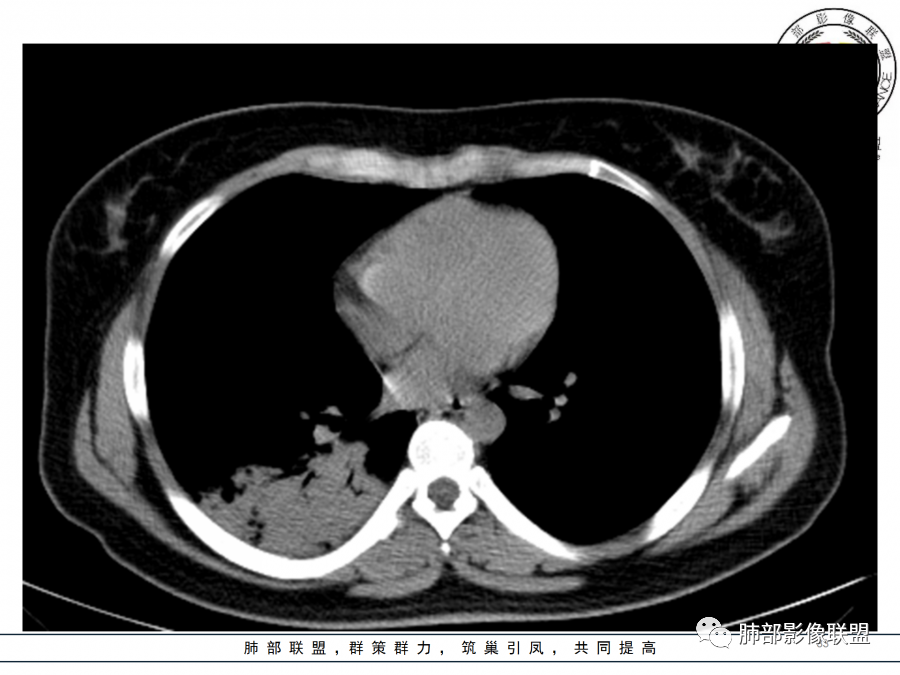

右肺胸膜下实变,病变跨多个叶生长,宽基底与胸膜相连,近端支气管穿行病灶内,并可见片状磨玻璃影,边界清,部分远端小支气管堵塞,支气管略有扩张,周围散发小结节,临床年轻女性,炎性指标高,发热六日,首先考虑感染性病变(肺链,奴卡,隐球,OP)鉴别淋巴瘤。

年轻女性,无明显诱因发热,体温略高,起病较急,有畏寒,右下肺紧贴胸膜下片状实变影,部分融合,外围有结节影,性质比较单一,类似于蘑菇兄弟,病灶周围伴有晕,支气管进入近端扩张远端堵塞,常规考虑感染,肺炎链球菌、隐球菌。

青年女性,发热咳嗽5天,炎症标志物升高。右肺下叶大片实变伴周围GGO,GGO内未见细网格,主体与胸膜平行,似多个病灶融合,实变区内见支气管部分进入,部分支气管受压狭窄,周围可见多发卫星病灶。支持炎性,考虑隐球感染,鉴别op。

年轻女性,急性起病,咳嗽,发热,黄痰,白细胞高,CRP基本正常,基础体健。CT提示右肺下叶实变,宽基底与胸膜相连,长轴平行于胸膜,可见支气管充气征,于病变中央截断,走形自然,胸膜下脂肪间隙可见,倾向于隐球菌,鉴别肺链,军团菌等。

26岁,女性,发热、咳嗽5天。咳少量黄痰,起病急,病程短,白细胞及中性高,血沉及D-二聚体增高。胸部CT:右肺下叶大片实变,长轴沿胸膜分布,宽基底与胸膜接触,边界不清,周围GGO,部分团片影融合,病灶内可见支气管充气征,部分支气管进入病灶后阻塞。考虑:感染性病变,隐球菌?脓毒肺栓塞?鉴别:肺炎型肺Ca。

年轻女性,急性病史,发热,WBC17.42*10^9/L,NE%82.8%,

痰革兰染色示:G-杆菌1+、G+球菌1+,未检出真菌,抗酸染色阴性。

大片实变影

细菌性感染?隐球菌?结核?梗死?

淋巴瘤?肺炎型肺癌?支原体?病毒?